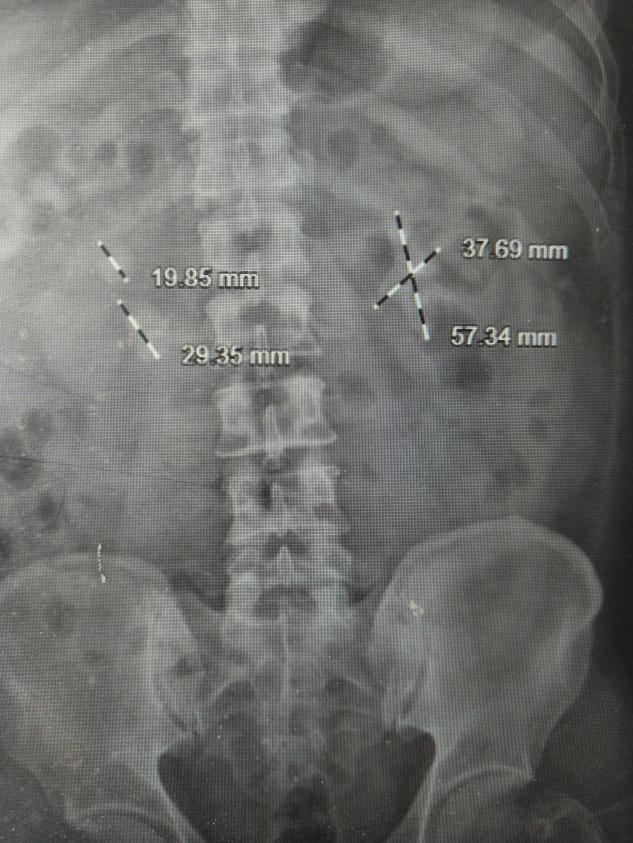

如果一个人体内有几颗大石头,会怎么样?今天故事的主角朱先生,是一位糖尿病患者,就曾与这样的石头“共处”了许多年。这些石头长满他的两个肾脏,形成医学上最复杂、处理难度极高的“多发铸形结石”。

许多年前的一次体检,朱先生得知自己患有双肾结石。因当时症状不明显,也未规律复查。时间一晃而过。近期,朱先生时常感到腰部隐隐酸胀,体力也大不如前。他原以为是年纪大了的正常现象,直到一次剧烈的腰痛发作,才在家人的催促下就医,检查结果让他和家人都大吃一惊。CT显示,他的双肾结石,其中左肾几乎填满了各个肾盏,合并积水及感染,并且明确糖尿病,血糖超高。

“就像一个模具里灌满了石膏,结石完全依照肾脏内部的空腔形状生长,处理起来非常棘手。”泌尿外科主任、副主任医师刘伟光介绍,“尤其朱先生还有糖尿病,这大大增加了手术的复杂性和感染风险。”